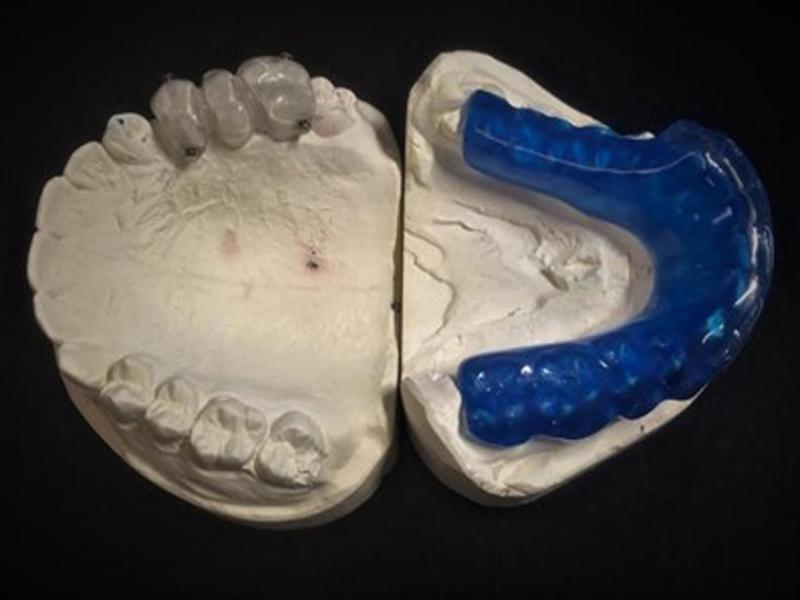

Figure 4.